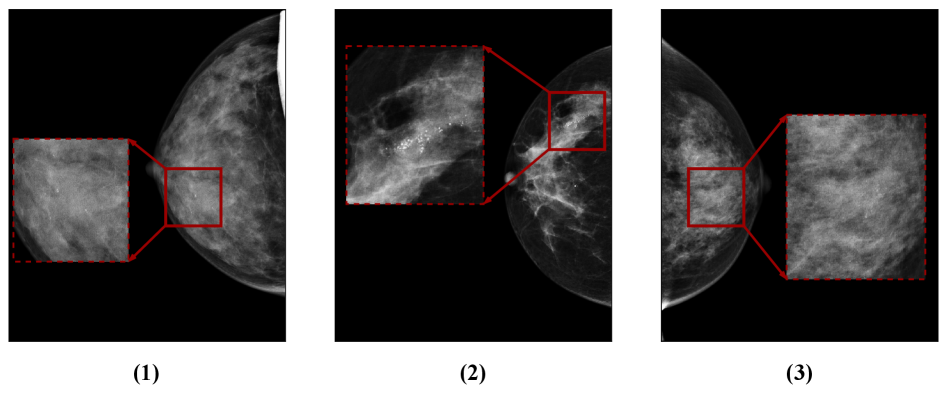

Laterality flipping: Some datasets suffer from laterality inconsistencies, where the laterality information in the image headers does not match the actual side of the breast [48], or the laterality is correct but the image itself has been horizontally flipped. Ensuring consistent and accurate laterality annotation is a critical step in dataset preparation, particularly for four-view image analysis. A common pre-processing approach involves horizontally flipping one breast side to achieve consistency and facilitate ipsi-lateral comparisons, thereby improving feature extraction [12, 13, 17]. In certain datasets these issues have been documented, whereas in others they require careful verification. See Figure 4, where all images are from the R-CC view but exhibit different laterality, illustrating this issue.

Processing of the imaging data began with normalizing the images to ensure a consistent dynamic bit range across all cases. Subsequently, each image was checked for laterality, and to maintain consistency, images with right laterality were horizontally flipped, resulting in a uniform orientation. Following this step, an additional procedure was applied to identify images with flipped intensity and correct them accordingly. Figure 9 illustrates the overall process with representative examples. Approximately 28% of the images in the CBIS-DDSM dataset were identified with flipped laterality issues, and about 23% of the images in the VinDr-Mammo dataset exhibited flipped intensity artifacts.